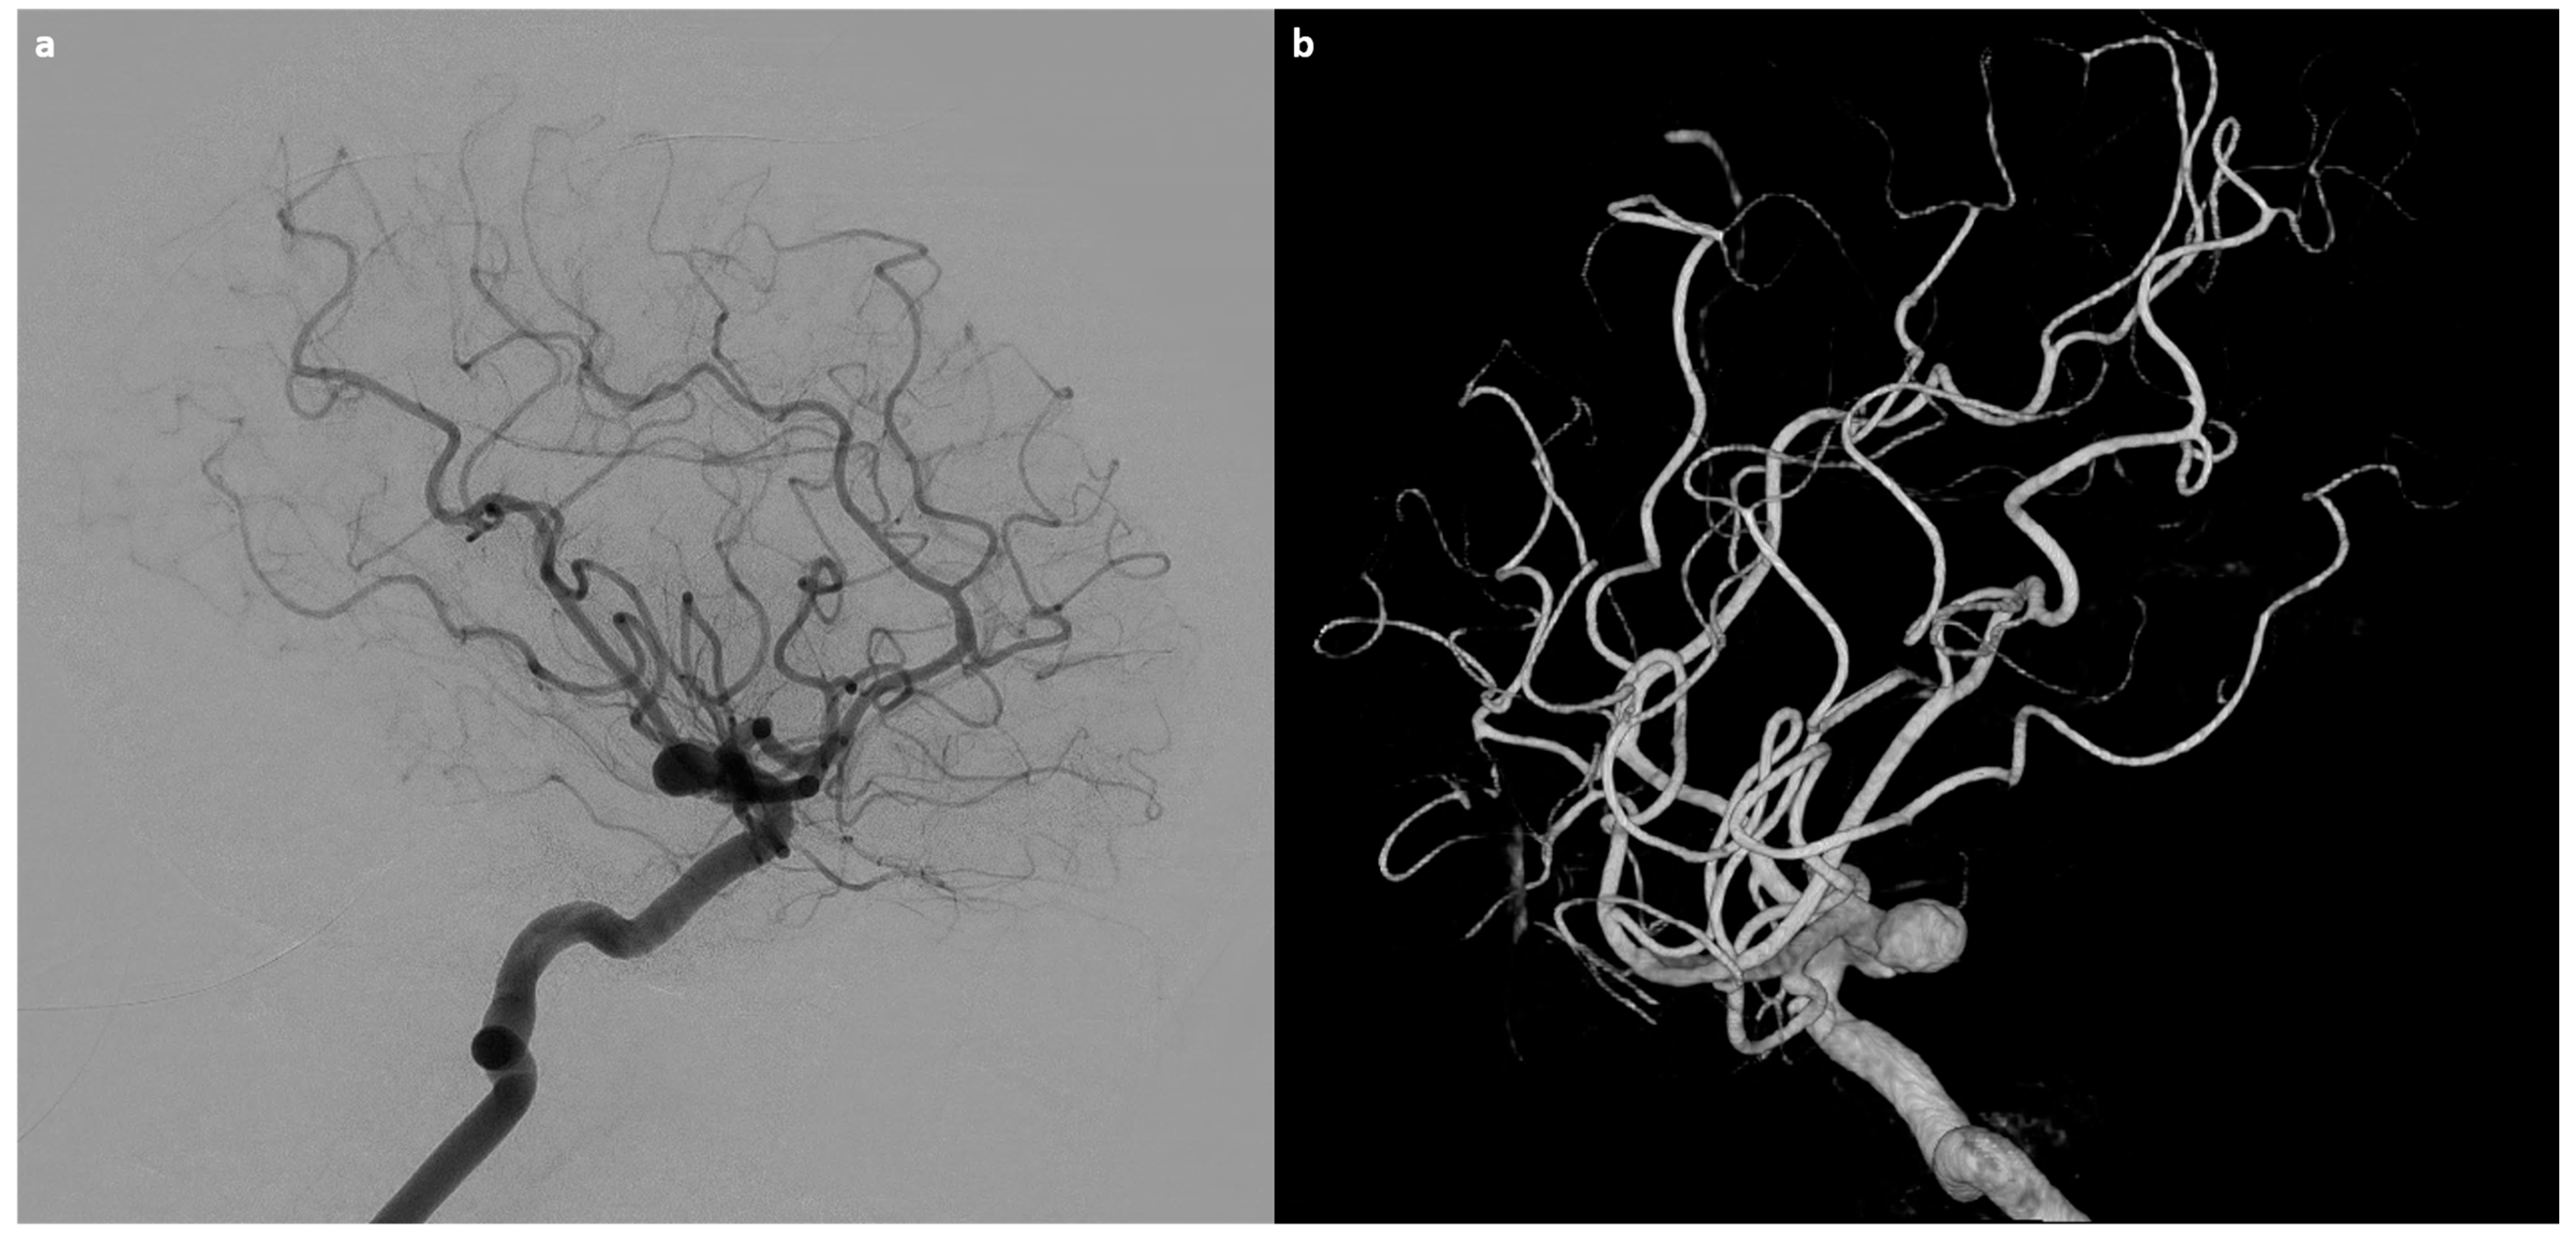

- Gallas, S.; Tuilier, T.; Ebrahiminia, V.; Bartolucci, P.; Hodel, J.; Gaston, A. Intracranial aneurysms in sickle cell disease: Aneurysms characteristics and modalities of endovascular approach to treat these patients. J. Neuroradiol. 2019, 47, 221–226. [Google Scholar] [CrossRef]